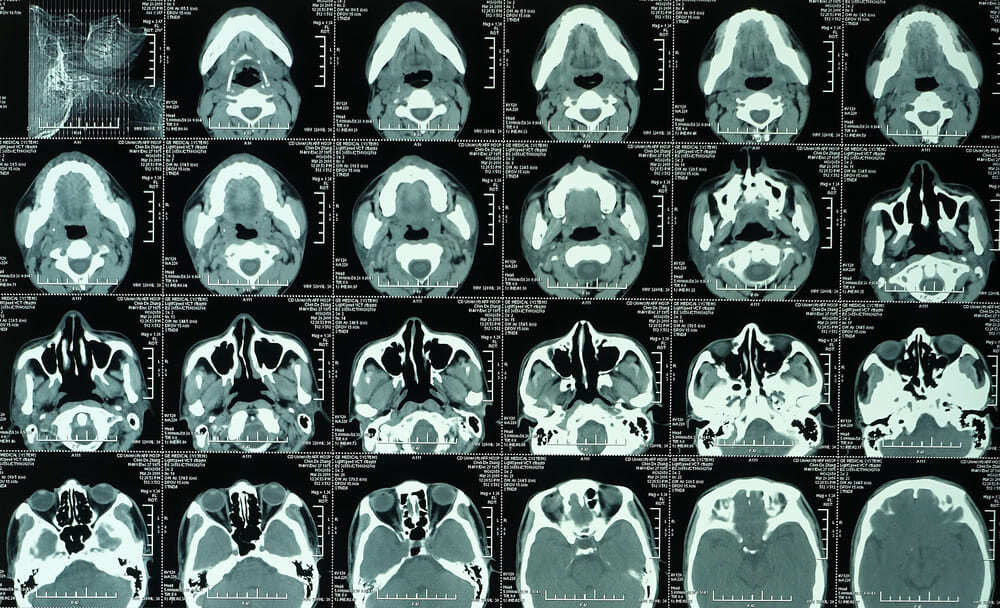

Advanced Multislice CT Scans: What Makes Them More Accurate?

Advanced Multislice CT Scan

If you’re looking for a CT scan in Brooklyn, NY, you can start at City Wide Radiology. According to a 2021 report by Frost & Sullivan, 375 million CT scans happen worldwide. Still, when your doctor orders a CT scan in NYC, and you want to know it will actually catch what is wrong, the technological details matter. […]